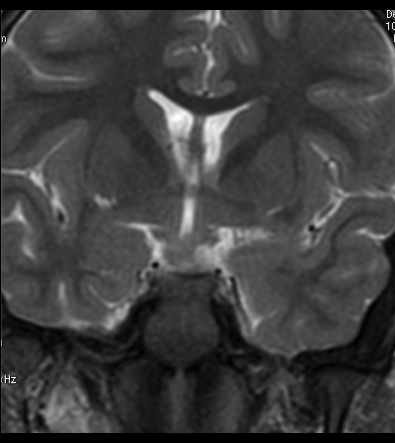

Niña de 7 años. Se solicita RM hipofisaria por pubertad precoz.

1. ¿Cuál es tu diagnóstico?

- A. Glioma hipotalámico.

- B. Histiocitosis X.

- C. Hamartoma hipotalámico.

- D. Craneofaringioma.

- E. Germinoma hipotalámico.